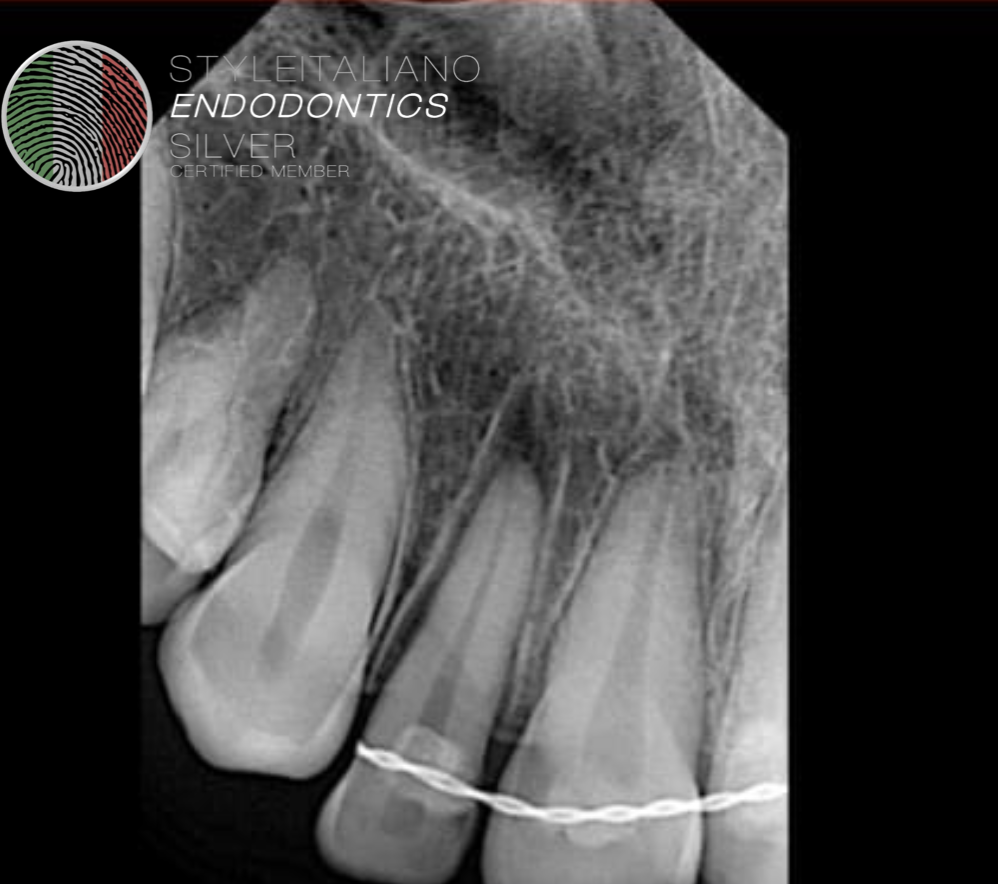

Fig. 4

Patient was not able to report on time. And root resorption was seen after 2 months time.